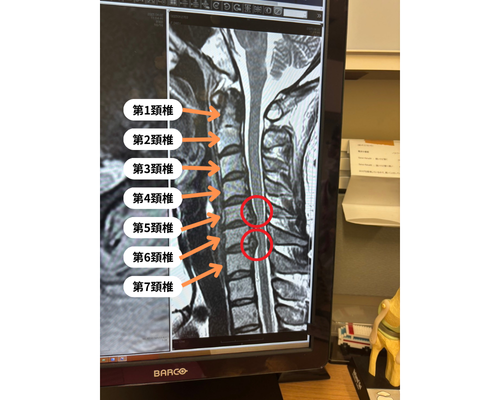

当院に来院される前に、病院でMRI検査を受けて第5頚椎と第6頚椎間、第6頚椎と第7頚椎間の頚椎ヘルニアの指摘を受けて内服薬も処方されて経過を見ていましたが、なかなか改善されず頚椎の手術も提案を受けたそうです。

実際のMRI画像です。(お客様に許可を頂き掲載させていただきました)